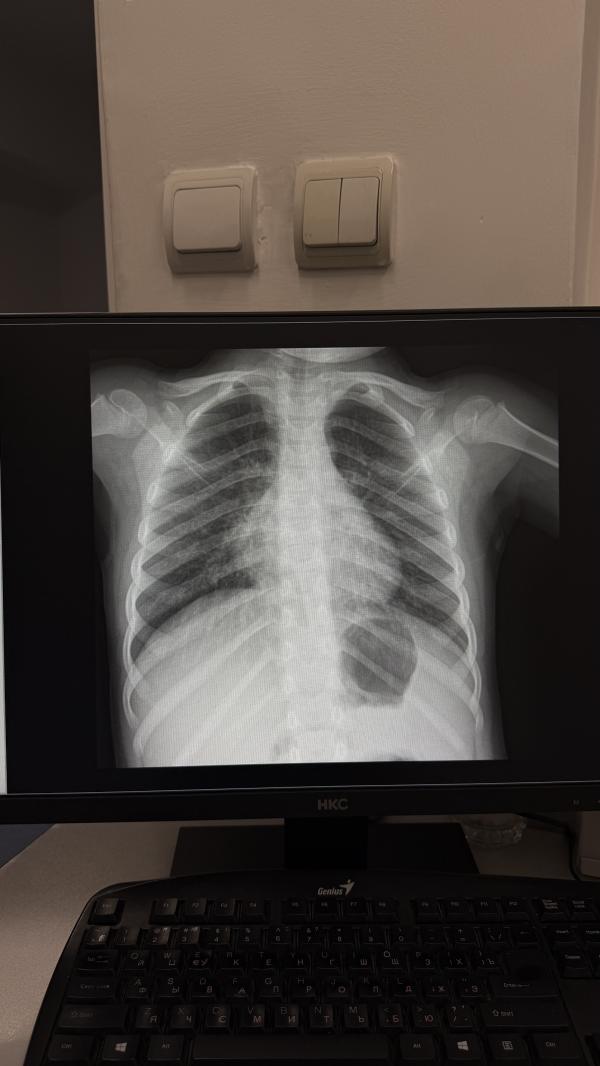

Девочки, у дочери температура уже несколько дней, кашель уже на протяжении 2-3 месяцев (не коклюш). Поехали во вторую детскую, там послушали ее, сказали все нормально, по моей просьбе сделали рентген. Проверили на моем телефоне и сказали за секунду «чисто» и все. Отправили домой. Больше никакой проверки, никакой рекомендации. Не знаю что нужно делать, чтобы некоторые врачи осмотрели как следует ребенка. Я не про всех, бывают такие странные. «Зачем вы вообще вечером приехали? Это не серьезный слу...